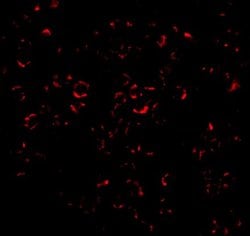

Invitrogen™ MCL-1 Polyclonal Antibody

A suggested positive control is Raji cell lysate. PA5-20121 can be used with blocking peptide PEP-0239.

| Applications | Western Blot, Immunocytochemistry |